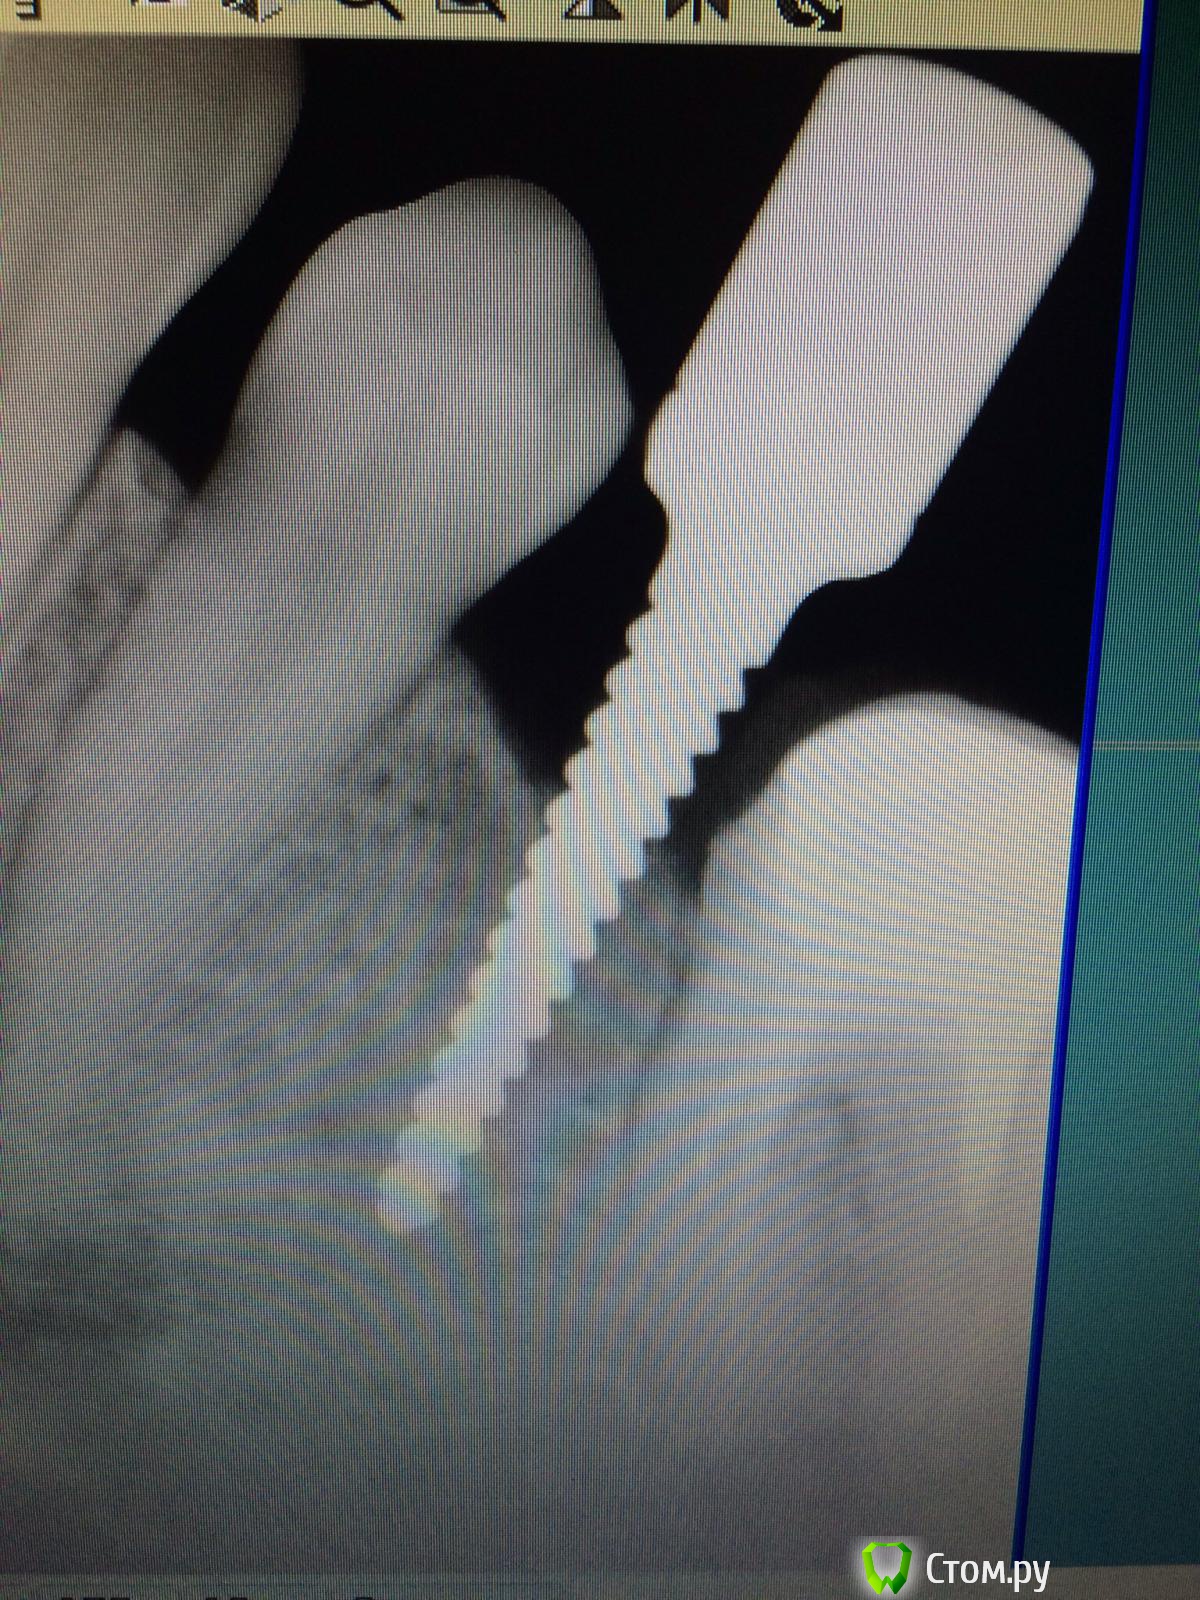

Vadim09 Опубликовано 3 октября, 2014 Поделиться Опубликовано 3 октября, 2014 (изменено) В области 3.5 отсутствует зуб, планирую поставить имплантиум 3.8, с расщеплением и подсадкой кости мис 4bone и мембраной от мис, подскажите тонкости, чтобы не сделал ошибку и простите, если вопрос не корректный. Изменено 3 октября, 2014 пользователем Vadim09 Ссылка на комментарий

doc-евгений Опубликовано 4 октября, 2014 Поделиться Опубликовано 4 октября, 2014 Имплантат 3.6 с нкр, без расщепления. Гребень с поднутрением, большая вероятность отлома. Ссылка на комментарий

faity Опубликовано 4 октября, 2014 Поделиться Опубликовано 4 октября, 2014 Расщепление не надо- может лопнуть. Ложе будете готовить пилотом пройдите, потом остеотомами работайте до нужного размера ,сверху стружки сыпануть. Ссылка на комментарий

Vadim09 Опубликовано 4 октября, 2014 Автор Поделиться Опубликовано 4 октября, 2014 (изменено) Расщепление не надо- может лопнуть. Ложе будете готовить пилотом пройдите, потом остеотомами работайте до нужного размера ,сверху стружки сыпануть.Спасибо, воспользовался вашим советом, кортикалка лопнула у шейки немног, пдсыпал биоосса и покрыл мембраной Изменено 4 октября, 2014 пользователем Vadim09 Ссылка на комментарий

k.t.m. Опубликовано 4 октября, 2014 Поделиться Опубликовано 4 октября, 2014 Спасибо, воспользовался вашим советом, кортикалка лопнула у шейки немног, пдсыпал биоосса и покрыл мембранойimage.jpgimage.jpgнадо было заглубить и более медиальнее 3 Ссылка на комментарий

Vadim09 Опубликовано 4 октября, 2014 Автор Поделиться Опубликовано 4 октября, 2014 (изменено) надо было заглубить и более медиальнееТоже так подумал, какя-то боязнь задеть корни, после того как у одного опытного доктора увидел.Когда раскрою, выложу фото и буду рад критике и советам Изменено 4 октября, 2014 пользователем Vadim09 Ссылка на комментарий